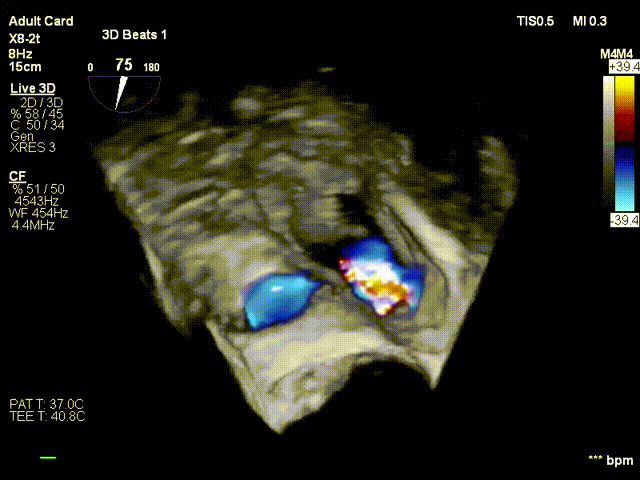

2. Steer and rotate the delivery system toward the target; advance and deploy the anchoring screw under 3D MPR plane guidance

3. After adjusting orientation, position the clamping arms for landing